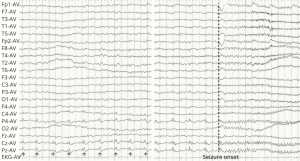

Take our EEG Test Questions!

Are you prepping for your EEG boards? 🧠📚

Do you just like engaging in posts about the NDT field? ✔

Engage with our community and enhance your knowledge in the neurodiagnostic field with our EEG Fun Facts. Each fact comes with a question and multiple choice answer to choose from to test your knowledge!